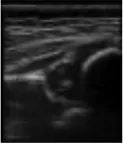

In this study, the GE LOGIQ-E9 ultrasonic diagnostic instrument (America) and 9l linear probe with a frequency range of 5.0–9.0 MHz were employed for imaging of the hip joint. The ultrasound coronal plane of Graf’s method was chosen as the standard imaging technique for this purpose. The imaging procedures were conducted by experienced senior physicians who possess the necessary expertise and technical skills in ultrasound imaging. In the standard imaging, four markers were identified, namely the iliac bone, bony rim point, lower iliac limb point, and glenoid labrum, as illustrated in Figure 2. These markers were selected based on their ability to provide accurate and reliable measurements of the hip joint. The utilization of a standardized imaging protocol and the identification of these markers allowed for consistent and reproducible imaging of the hip joint, ensuring the validity and reliability of the data obtained in this study.

FIGURE 2

www.frontiersin.org

Figure 2. Measurement of the neutral coronal plane of the hip joint using the graf method. (A) Iliac bone, (B) bony rim point, (C) lower iliac limb point, (D) glenoid labrum.